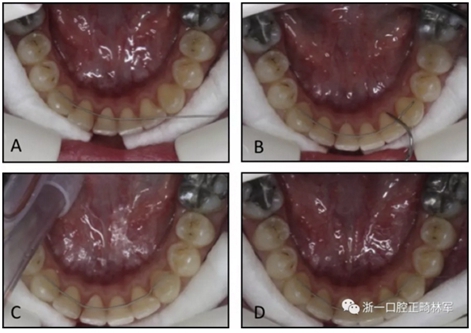

在第二組中,保持器直接粘結(jié)。首先,用與第1組相同的粘接劑將極軟的保持弓絲粘接到左側(cè)尖牙上,然后將弓絲被動(dòng)地與其他尖牙和切牙的舌側(cè)表面相適應(yīng)。極軟弓絲使臨床醫(yī)生能夠使用手持儀器輕松彎曲保持器(圖2)。下頜切牙和另一個(gè)尖牙用相同的粘接劑底漆和糊劑粘接。所有的保持器都由同一個(gè)擁有超過(guò)2年臨床經(jīng)驗(yàn)的研究員(F.G.)粘接。在兩組拔牙患者中,保持器達(dá)到了第一前磨牙。兩組上頜牙弓均采用壓模保持器。

圖2. 第二組,在沒(méi)有石膏模型的情況下制備極軟的保持弓絲:A,極軟的保持弓絲與左側(cè)尖牙粘接; B-D,然后弓絲被動(dòng)地適應(yīng)并粘接到其他牙齒。